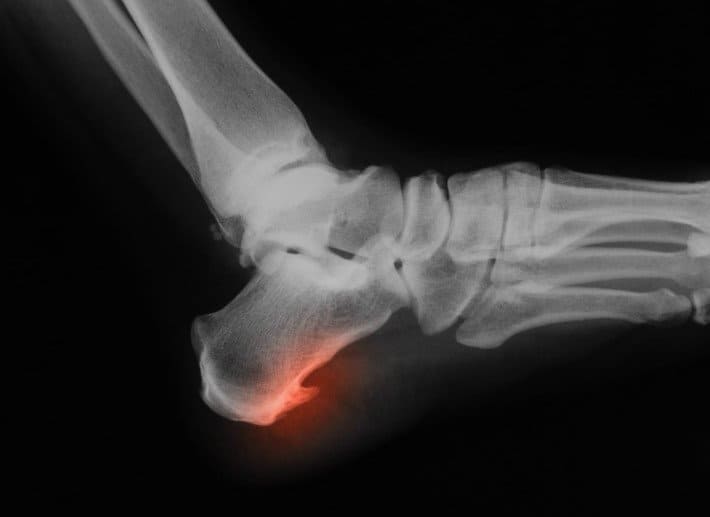

Пяточная шпора – это кальцинированный нарост на пяточной кости, так называемый остеофит. Он может образоваться в результате травмы, ревматизма, плоскостопия, а также больших физических нагрузок, в результате чего нагрузка большей частью оказывается в области стопы. В эти моменты, сухожилия пятки надрываются и травмируются, при этом воспаленные сухожилия, постепенно замещаются рубцом. Этот рубец является благоприятным местом для отложения кальциевых отложений, которые со временем образуют костный кальцинированный выступ – пяточную шпору, который можно легко увидеть на рентгеновском снимке.

Пяточная шпора – это кальцинированный нарост на пяточной кости, так называемый остеофит. Он может образоваться в результате травмы, ревматизма, плоскостопия, а также больших физических нагрузок, в результате чего нагрузка большей частью оказывается в области стопы. В эти моменты, сухожилия пятки надрываются и травмируются, при этом воспаленные сухожилия, постепенно замещаются рубцом. Этот рубец является благоприятным местом для отложения кальциевых отложений, которые со временем образуют костный кальцинированный выступ пяточную шпору, который можно легко увидеть на рентгеновском снимке.